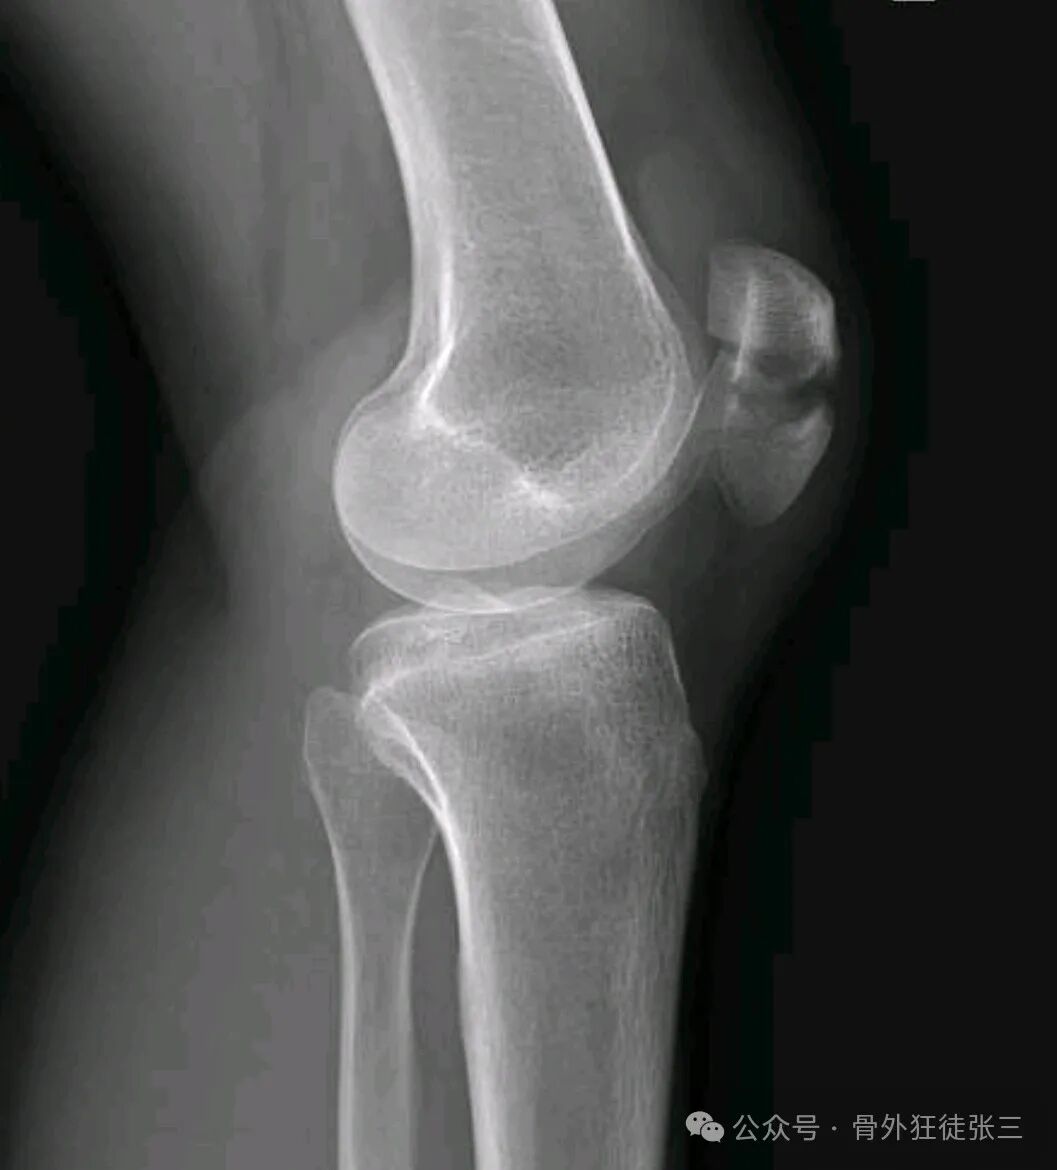

【患者信息】:男,56岁

【主诉】:摔伤左膝关节致肿痛、活动受限2天。

【现病史及既往史】:2天前摔伤左膝关节,就诊当地医院,行石膏固定,患者无法忍受石膏固定,无法忍受卧床,要求手术治疗,早日下床,为求治疗,来院。

【临床诊断】:左髌骨骨折